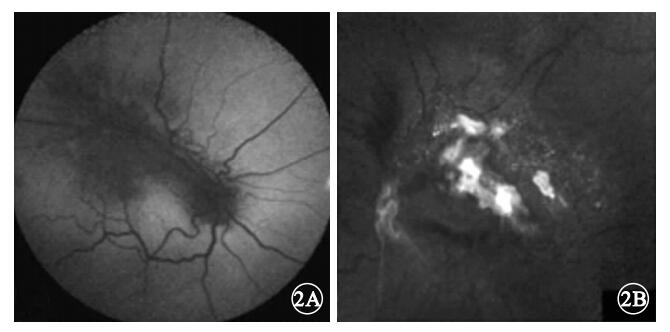

AF檢查發現,8只眼中,病灶隆起處及其周圍色素沉著區域AF亮度降低(圖 2A)7只眼,占87.5%;AF亮度增強部位與病灶表面致密的前膜相對應(圖 2B)1只眼,占12.5%。

AF檢查發現,8只眼中,病灶隆起處及其周圍色素沉著區域AF亮度降低(圖 2A)7只眼,占87.5%;AF亮度增強部位與病灶表面致密的前膜相對應(圖 2B)1只眼,占12.5%。

Font等[2]通過摘除誤診為脈絡膜黑色素瘤的CHRRPE患眼行病理學檢查,發現瘤體內組織層次不清,主要由雜亂的視網膜血管、膠質及增生的RPE細胞構成。不同CHRRPE病灶內膠質或RPE細胞的成份各有不同,可能主要以膠質增生為主,也可能以增生的RPE細胞為主,但血管成份較少。這些增生的RPE細胞可位于外層視網膜,也可位于內層視網膜或瘤體表面[3, 4]。AF圖像能夠顯示RPE內脂褐質的含量與分布,可依此評價RPE的代謝狀況。我們發現,7只眼的CHRRPE病灶及其周圍色素沉著區域AF亮度降低。說明CHRRPE病灶沒有產生AF的物質。而CHRRPE病灶周圍沉著的色素導致其下方RPE因遮蓋也無AF產生。說明CHRRPE病灶周圍色素沉著并非與此區域RPE細胞異常增生有關,這些色素的來源仍待研究。但根據AF亮度降低的范圍可判斷CHRRPE病灶及其周圍色素沉著的面積。我們還發現,1只眼的病變部位有局灶性AF亮度增強表現,其分布與CHRRPE病灶表面致密的纖維膜相對應。我們認為這可能與致密纖維膜對激發光的強反射有關。

Font等[2]通過摘除誤診為脈絡膜黑色素瘤的CHRRPE患眼行病理學檢查,發現瘤體內組織層次不清,主要由雜亂的視網膜血管、膠質及增生的RPE細胞構成。不同CHRRPE病灶內膠質或RPE細胞的成份各有不同,可能主要以膠質增生為主,也可能以增生的RPE細胞為主,但血管成份較少。這些增生的RPE細胞可位于外層視網膜,也可位于內層視網膜或瘤體表面[3, 4]。AF圖像能夠顯示RPE內脂褐質的含量與分布,可依此評價RPE的代謝狀況。我們發現,7只眼的CHRRPE病灶及其周圍色素沉著區域AF亮度降低。說明CHRRPE病灶沒有產生AF的物質。而CHRRPE病灶周圍沉著的色素導致其下方RPE因遮蓋也無AF產生。說明CHRRPE病灶周圍色素沉著并非與此區域RPE細胞異常增生有關,這些色素的來源仍待研究。但根據AF亮度降低的范圍可判斷CHRRPE病灶及其周圍色素沉著的面積。我們還發現,1只眼的病變部位有局灶性AF亮度增強表現,其分布與CHRRPE病灶表面致密的纖維膜相對應。我們認為這可能與致密纖維膜對激發光的強反射有關。